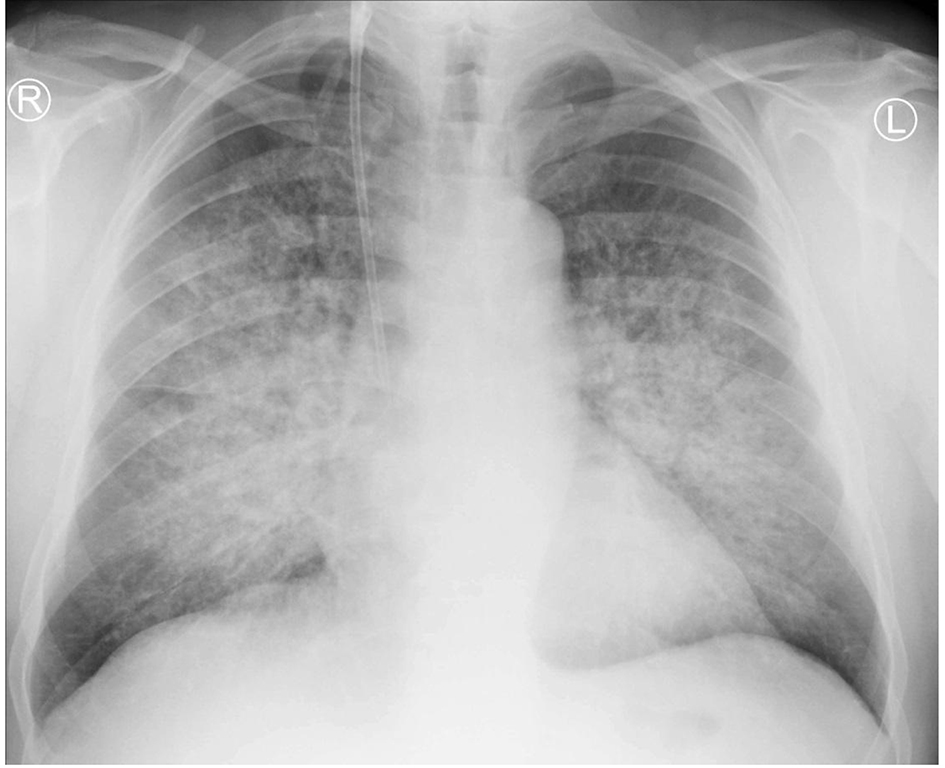

A 59-year-old previously healthy man, a long-standing cigarette smoker, presented to a local community hospital emergency department with acute kidney injury (AKI) with progressive oliguria, dyspnea, cruses edema and elevated blood pressure. Two weeks before hospitalization, he had lumbar pain, polyuria, hematuria and proteinuria and was unsuccessfully treated with ciprofloxacin. There was no another previous history of renal or pulmonary disease. No family disease was known and he had also no other relevant findings in his past medical history. Upon admission, his chief complaint was malaise and weakness. Laboratory data revealed elevated levels of serum creatinine of 10.3 mg/dL, fulfilling the requirements of third stage of AKI according to KDIGO criteria, blood urea nitrogen level of 78.5 mg/dL, normocytic normochromic anemia with hemoglobin level of 8.8 g/dL and slightly elevated C-reactive protein level of 22 mg/L. Urinalysis showed active urine sediment with numerous dysmorphic red blood cells and non-nephrotic range proteinuria. Chest radiograph revealed diffuse pulmonary infiltration (Fig. 1). His oxygen saturation was 95% on 21% oxygen with no signs of carbon dioxide retention.

![]() Click for large image | Figure 1. Chest X-ray revealing bilateral diffuse alveolar infiltration spreading from hilums. |